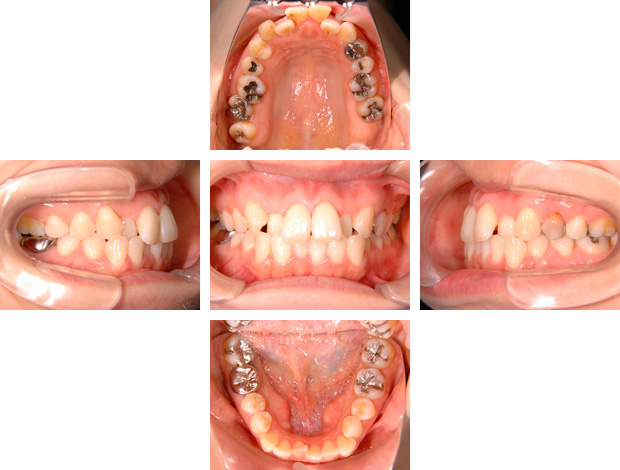

治療前

叢生、前歯の傾斜、口元の突出感があり、非抜歯で治療すると前歯の傾斜、口元の突出感は悪くなることが予想されました。

そのため話し合いの結果、上下左右第一小臼歯の抜歯を行い、三十代であったため歯周組織へのダメージを考慮しながら、約3年の期間をかけて治療した症例です。